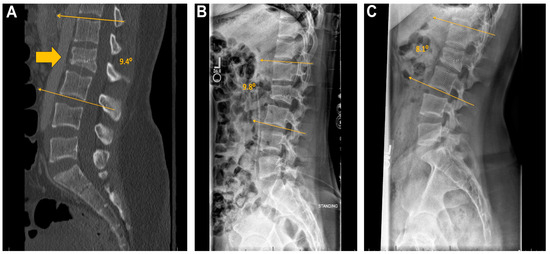

2.4. Alignment

3.7. Alignment

4.6. Alignment